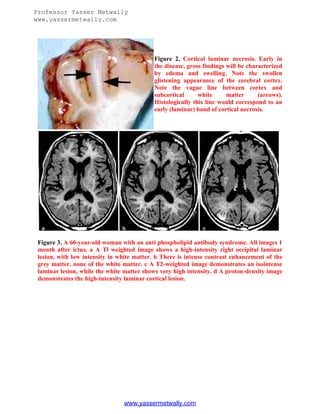

Figure 2. Cortical laminar necrosis. Early in

the disease, gross findings will be characterized

by edema and swelling. Note the swollen

glistening appearance of the cerebral cortex.

Note the vague line between cortex and

subcortical

white

matter

(arrows).

Histologically this line would correspond to an

early (laminar) band of cortical necrosis.

Figure 3. A 60-year-old woman with an anti phospholipid antibody syndrome. All images 1

month after ictus. a A Tl weighted image shows a high-intensity right occipital laminar

lesion, with low intensity in white matter. b There is intense contrast enhancement of the

grey matter, none of the white matter. c A T2-weighted image demonstrates an isointense

laminar lesion, while the white matter shows very high intensity. d A proton-density image

demonstrates the high-intensity laminar cortical lesion.